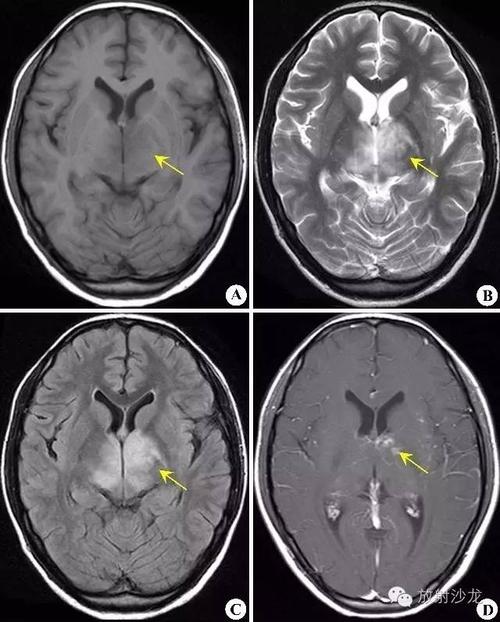

脑白质软化,脑白质脱髓鞘

新生儿脑室周围白质软化的影像学特点

zt0163:早产儿脑室周围白质软化(pvl)